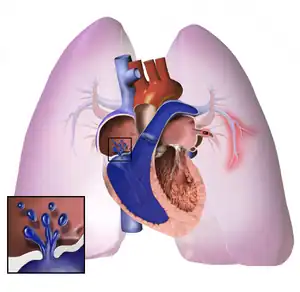

The pathogenesis of pulmonary arterial hypertension (WHO Group I) involves the narrowing of blood vessels connected to and within the lungs. This makes it harder for the heart to pump blood through the lungs, as it is much harder to make water flow through a narrow pipe as opposed to a wide one. Over time, the affected blood vessels become stiffer and thicker, in a process known as fibrosis. The mechanisms involved in this narrowing process include vasoconstriction, thrombosis, and vascular remodeling (excessive cellular proliferation, fibrosis, and reduced apoptosis/programmed cell death in the vessel walls, caused by inflammation, disordered metabolism and dysregulation of certain growth factors).[25][26] This further increases the blood pressure within the lungs and impairs their blood flow. In common with other types of pulmonary hypertension, these changes result in an increased workload for the right side of the heart.[14][27] The right ventricle is normally part of a low pressure system, with systolic ventricular pressures that are lower than those that the left ventricle normally encounters. As such, the right ventricle cannot cope as well with higher pressures, and although right ventricular adaptations (hypertrophy and increased contractility of the heart muscle) initially help to preserve stroke volume, ultimately these compensatory mechanisms are insufficient; the right ventricular muscle cannot get enough oxygen to meet its needs and right heart failure follows.[14][26][27] As the blood flowing through the lungs decreases, the left side of the heart receives less blood. This blood may also carry less oxygen than normal. Therefore, it becomes harder and harder for the left side of the heart to supply sufficient oxygen to the rest of the body, especially during physical activity.[28][29][10] During the end-systolic volume phase of the cardiac cycle, the Gaussian curvature and the mean curvature of right ventricular endocardial wall of PH patients was found to be significantly different as compared to controls.[30]

In PVOD (WHO Group I'), pulmonary blood vessel narrowing occurs preferentially (though not exclusively) in post-capillary venous blood vessels.[31] PVOD shares several characteristics with PAH, but there are also some important differences, for example differences in prognosis and response to medical therapy.

Persistent pulmonary hypertension of the newborn occurs when the circulatory system of a newborn baby fails to adapt to life outside the womb; it is characterized by high resistance to blood flow through the lungs, right-to-left cardiac shunting and severe hypoxemia.[14]

Pathogenesis in pulmonary hypertension due to left heart disease (WHO Group II) is completely different in that constriction or damage to the pulmonary blood vessels is not the issue. Instead, the left heart fails to pump blood efficiently, leading to pooling of blood in the lungs and back pressure within the pulmonary system. This causes pulmonary edema and pleural effusions.[32] In the absence of pulmonary blood vessel narrowing, the increased back pressure is described as 'isolated post-capillary pulmonary hypertension' (older terms include 'passive' or 'proportionate' pulmonary hypertension or 'pulmonary venous hypertension'). However, in some patients, the raised pressure in the pulmonary vessels triggers a superimposed component of vessel narrowing, which further increases the workload of the right side of the heart. This is referred to as 'post-capillary pulmonary hypertension with a pre-capillary component' or 'combined post-capillary and pre-capillary pulmonary hypertension' (older terms include 'reactive' or 'out-of-proportion' pulmonary hypertension).[12][16][33]